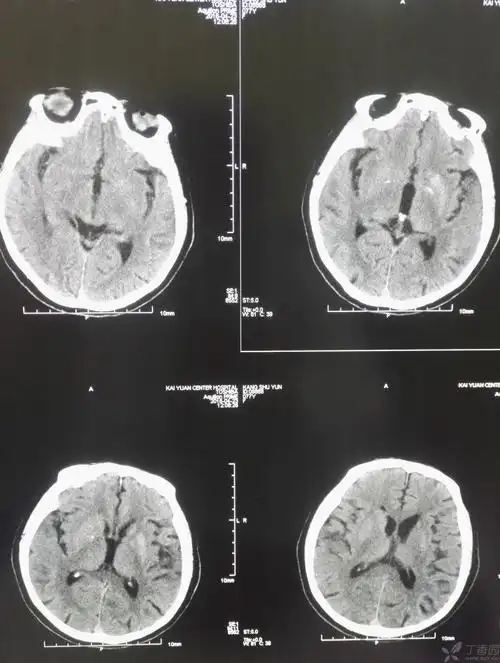

1月前发病时ct:左侧基底节区脑梗塞!

刘福君 左侧基底节区脑出血

头颅ct提示:左侧基底节区脑出血.出血量大于30ml.

头颅ct:右侧基底节区血肿,量约20ml.

头颅ct提示:左侧基底节区出血,出血量约35ml,右侧基底节区陈旧心栽

女,77岁,右侧肢体不灵一天,做头ct,左侧基底节区密度偏高,ct值41hu